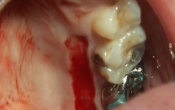

PARODONTOLOGIE

par

Thierry MOUSQUES

La greffe épithélio-conjonctive associée à une frénectomie. Présentation de 2 cas cliniques

Hervé ZEITOUN

La greffe épithélio-conjonctive ou autogreffe gingivale libre. Utilisation de l'épitome de Klewansky

32 min

Les autogreffes gingivales libres